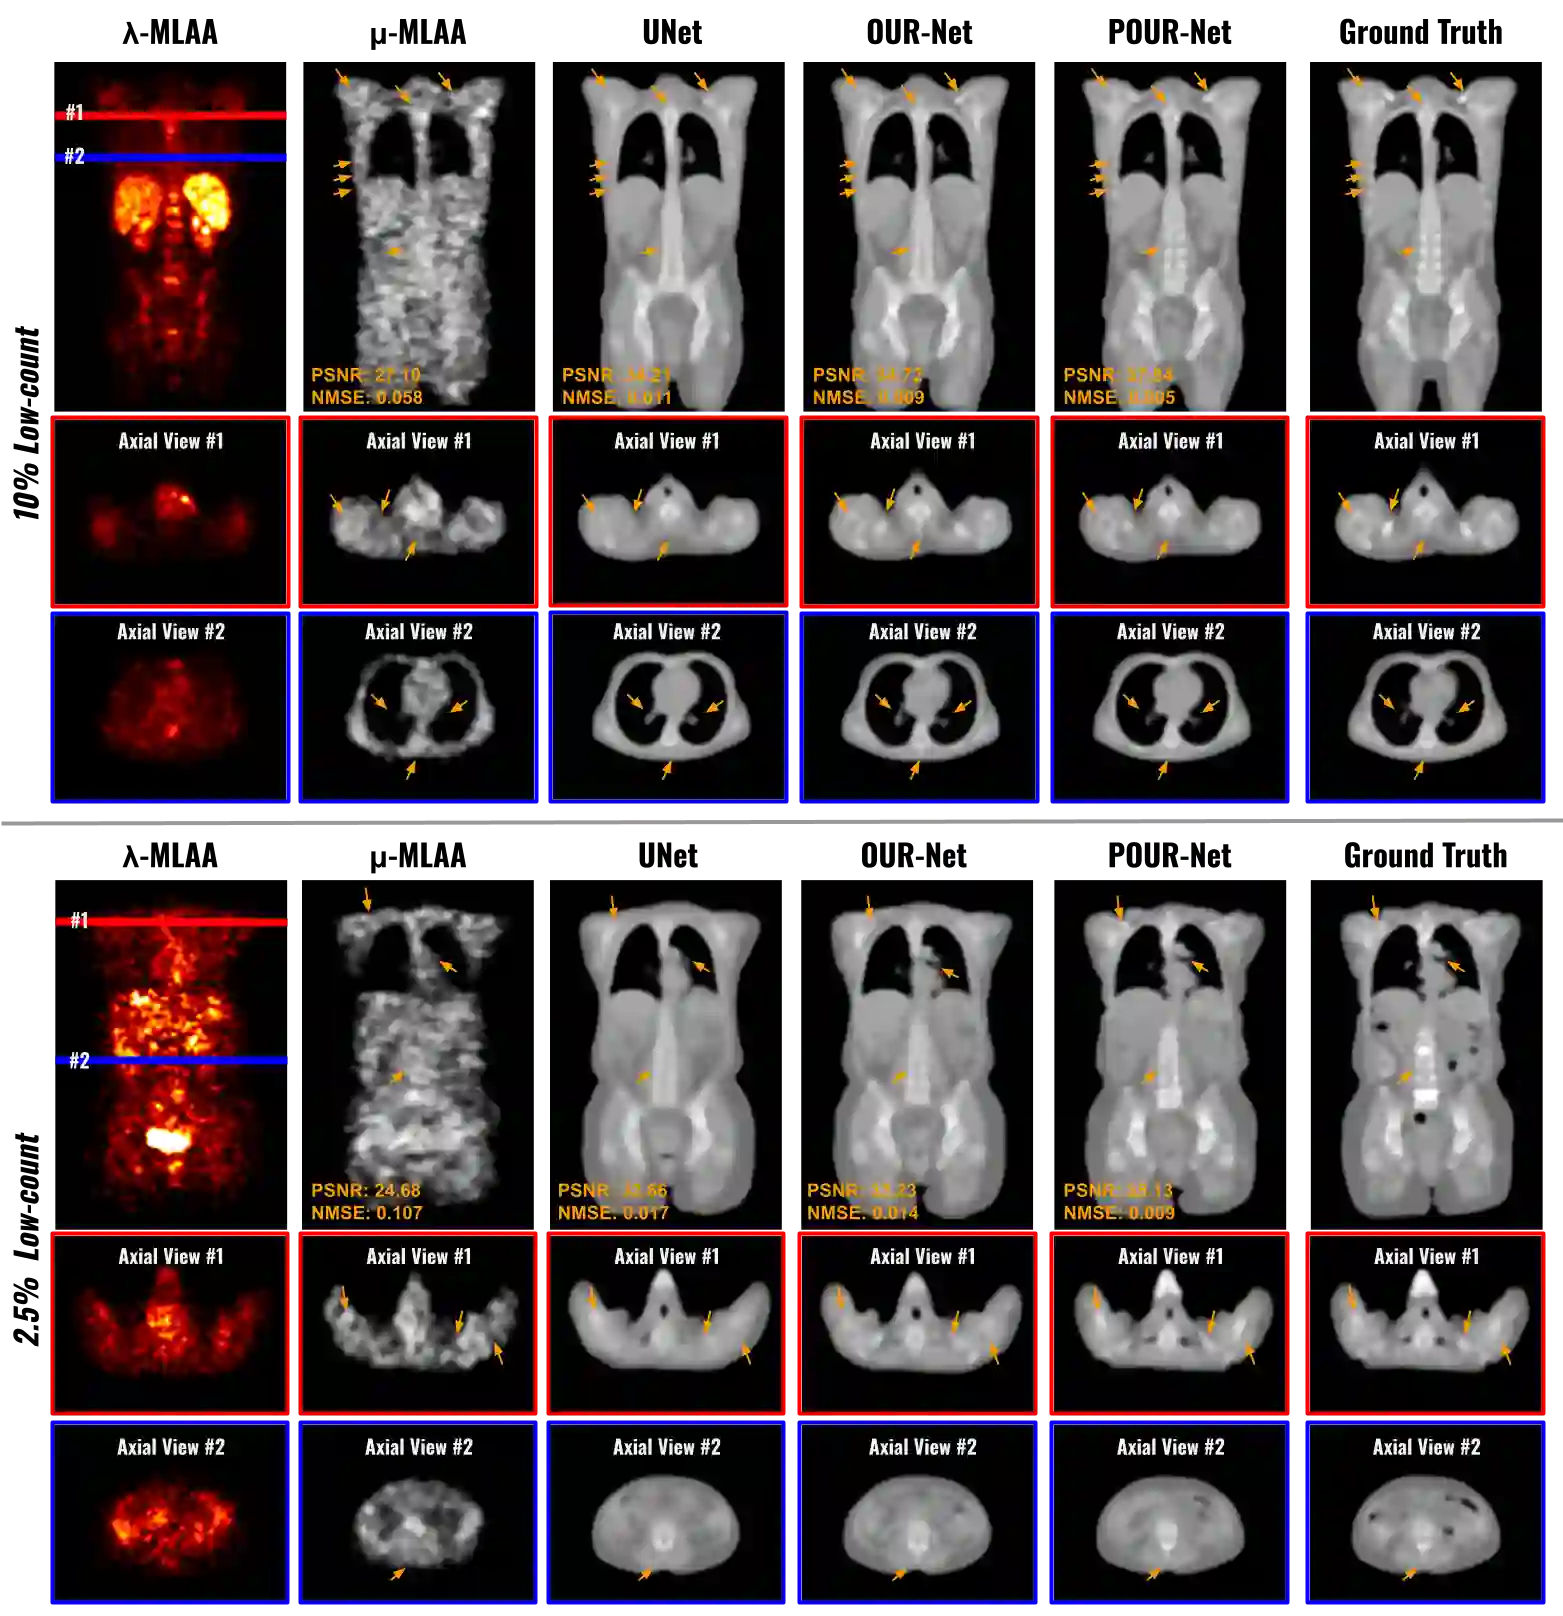

Low-dose PET offers a valuable means of minimizing radiation exposure in PET imaging. However, the prevalent practice of employing additional CT scans for generating attenuation maps (u-map) for PET attenuation correction significantly elevates radiation doses. To address this concern and further mitigate radiation exposure in low-dose PET exams, we propose POUR-Net - an innovative population-prior-aided over-under-representation network that aims for high-quality attenuation map generation from low-dose PET. First, POUR-Net incorporates an over-under-representation network (OUR-Net) to facilitate efficient feature extraction, encompassing both low-resolution abstracted and fine-detail features, for assisting deep generation on the full-resolution level. Second, complementing OUR-Net, a population prior generation machine (PPGM) utilizing a comprehensive CT-derived u-map dataset, provides additional prior information to aid OUR-Net generation. The integration of OUR-Net and PPGM within a cascade framework enables iterative refinement of $\mu$-map generation, resulting in the production of high-quality $\mu$-maps. Experimental results underscore the effectiveness of POUR-Net, showing it as a promising solution for accurate CT-free low-count PET attenuation correction, which also surpasses the performance of previous baseline methods.